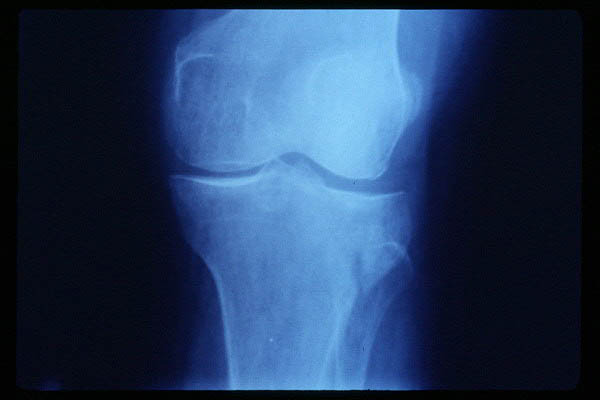

Prótesis completa de rodilla. Situación postquirúrgica.

Prótesis completa de rodilla. Situación postquirúrgica. Lateral.

Prótesis completa de rodilla.Lateral.

Prótesis completa de rodilla. Frontal.

Prótesis completa bilateral de rodillas.